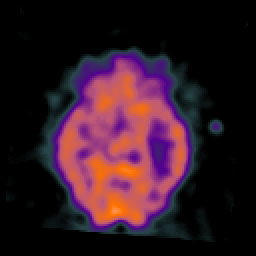

SPECT TC Study #3 -- Slice #23

[Home][Help][Clinical][Tour 1][Tour 2][Tour 3] Slice 23